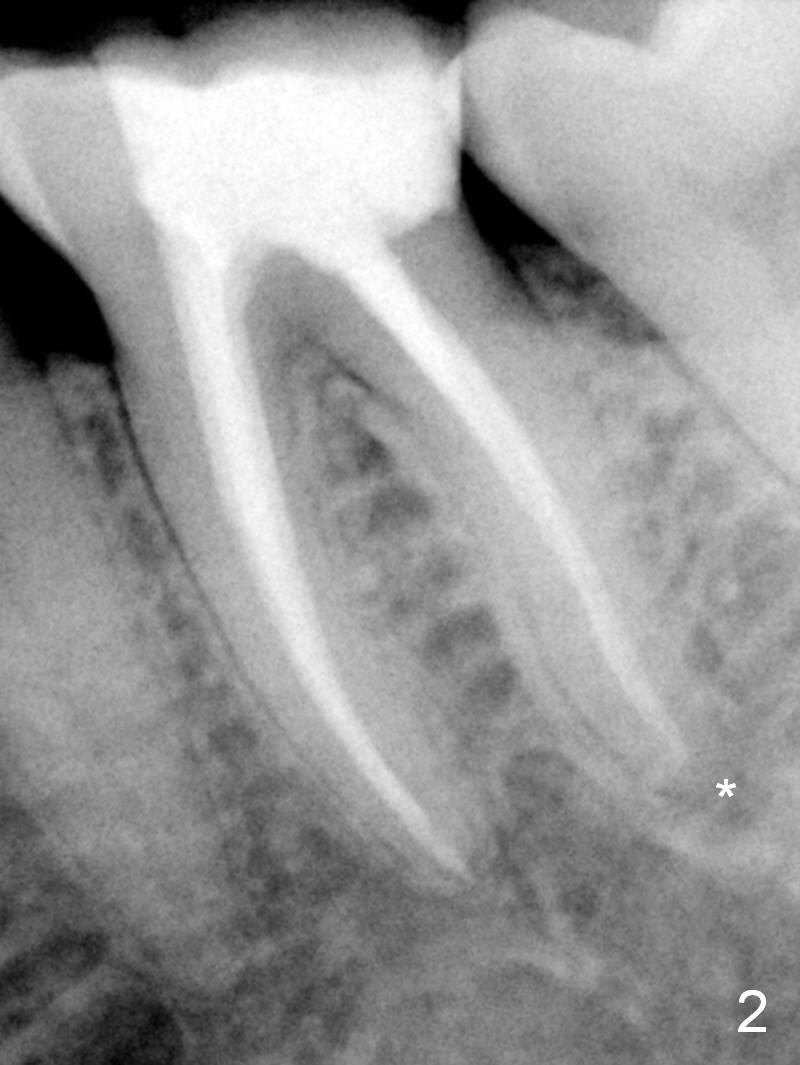

A 59-year-old woman had root canal therapy for the tooth #19 10.5 years ago (Fig.1 (red dashed line: the superior border of the Inferior Alveolar Canal). Two years later there was apparent periapical radiolucency with the distal root (Fig.2 *). The tooth remains asymptomatic until the last six months. There are 2 fistulae associated with the tooth: mesiolingual and buccal furca. Radiogra-phically, there are 2 radiolucent lesions: mesial and apical to the mesial root (Fig.3 *). If a 16 mm implant is placed, there will be approximately 5 mm apical bone (Fig.4); 7 mm for a 18 mm implant. The bone height is 25 mm (Fig.6). Therefore, once initial osteotomy is established with a 13 mm long drill with PA confirmation, the osteotomy is extended to its depth with 1.5x21 mm drill (Fig.5). After socket treatment with Metronidazole gauze with Epinephrine (1: 50,0000), take PVS impression of the socket to catch the large mesial defect. A fair amount of allograft and Osteogen is expected. It has been 9 months since last visit. Retake PA before surgery. If the mesial defect enlarges, start osteotomy in the distal slope of the septum.